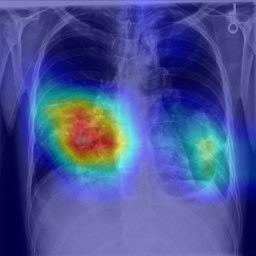

Large numbers of labeled medical images are essential for the accurate detection of anomalies, but manual annotation is labor-intensive and time-consuming. Self-supervised learning (SSL) is a training method to learn data-specific features without manual annotation. Several SSL-based models have been employed in medical image anomaly detection. These SSL methods effectively learn representations in several field-specific images, such as natural and industrial product images. However, owing to the requirement of medical expertise, typical SSL-based models are inefficient in medical image anomaly detection. We present an SSL-based model that enables anatomical structure-based unsupervised anomaly detection (UAD). The model employs the anatomy-aware pasting (AnatPaste) augmentation tool. AnatPaste employs a threshold-based lung segmentation pretext task to create anomalies in normal chest radiographs, which are used for model pretraining. These anomalies are similar to real anomalies and help the model recognize them. We evaluate our model on three opensource chest radiograph datasets. Our model exhibit area under curves (AUC) of 92.1%, 78.7%, and 81.9%, which are the highest among existing UAD models. This is the first SSL model to employ anatomical information as a pretext task. AnatPaste can be applied in various deep learning models and downstream tasks. It can be employed for other modalities by fixing appropriate segmentation. Our code is publicly available at: https://github.com/jun-sato/AnatPaste.

翻译:大量贴有标签的医学图像对于准确检测异常现象至关重要,但人工注解是劳动密集型和耗费时间的。自监学习(SSL)是一种培训方法,用于在不人工注解的情况下学习特定数据特征。一些基于SSL的模型被用于医学图像异常现象的检测。这些SSL方法有效地学习了多个特定领域图像的表解,如自然和工业产品图像。然而,由于医学专业知识的要求,基于SSL的典型模型在医学图像异常现象检测方面效率低下。我们展示了一个基于SSL的模型,可以进行基于解剖结构的、不受监督的异常现象检测(UAAD)。该模型使用解剖-觉粘贴(AnatPaste)增强工具。基于SSL的几种模型用于医学图像异常现象。这些异常现象与真正的异常相似,有助于模型识别这些异常现象。我们在三种开源的胸腔辐射数据集中可以使用模型,在基于解剖面结构结构的曲线下(AUSC),在92.1号中使用解析(Anal-SL)粘度图解为最高格式。